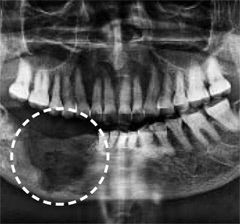

골다공증 치료제 투여 부작용으로 턱뼈가 괴사한 모습. 경향신문 자료사진 |

정상적인 뼈는 낡거나 손상된 조직을 제거하는 ‘골흡수’와 새로운 뼈를 만드는 ‘골형성’이 균형을 이뤄 유지된다. 하지만 골다공증 환자의 뼈는 골흡수 속도가 빨라져 점차 가늘고 약해진다. 치료를 위해선 골흡수를 억제해 골밀도를 유지·상승시키는 치료제인 ‘졸레드로네이트’나 ‘이반드로네이트’를 환자 상태에 맞춰 투여한다. 다만 약의 효과로 골흡수가 지나치게 억제되면 낡은 뼈가 잘 제거되지 않고 손상이 누적될 수 있는데, 특히 턱뼈는 이런 상태에서 발치나 임플란트 등 치료를 시행하면 회복이 지연돼 괴사로 이어지기 쉽다.

연구진은 발치 전 효과적인 골다공증 치료제 중단 시점을 분석했다. 그 결과 중단 기간이 길수록 턱뼈 괴사 발생 위험이 유의미하게 감소하는 것으로 나타났다. 턱뼈 괴사 발생률은 약물을 90일 이하 중단한 그룹(1.28%)에서 91~180일 중단한 그룹(0.71%), 365일 이상 중단한 그룹(0.42%)으로 갈수록 낮아졌다.